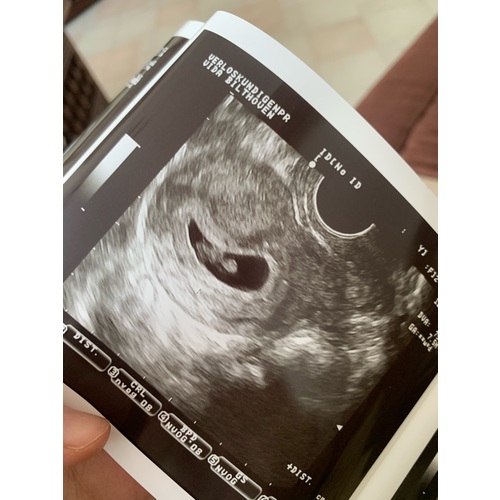

Inwendige echo: Zie je op de uitdraai van een inwendige echo de lichte vlek rechts in de baarmoeder? Dan verwacht je volgens de Ramzi-theorie een jongen. Wanneer je hem links in de baarmoeder ziet, zou je van een meisje in verwachting zijn.

Uitwendige echo: Als de echo via je buik is gemaakt, is de echo gespiegeld. Zie je op de uitdraai van de echo de lichte vlek rechts? Dan zou dit betekenen dat je een meisje krijgt. Een lichte vlek aan de linkerkant wijst bij een uitwendige echo op een jongen.

Bij mij is de echo inwendig genomen. Dan zou het volgens deze methode een meisje worden denk ik? Benieuwd wat de nipt als resultaat gaat geven ☺️

Oke dan ben ik heel erg benieuwd wat dit dan eventueel kan zijn volgens de ramzi methode dit is een inwendige echo geweest bij 8 weken zwangerschap